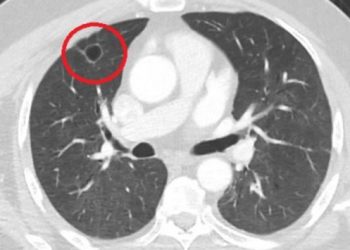

Devamını okuDetailsTekirdağ Dr. İsmail Fehmi Cumalıoğlu Şehir Hastanesi’nde, Covid-19’a yakalanan 500 hastanın yüzde 10’unda yeni başlayan kalp yetmezliği saptandı. Dünya Sağlık...